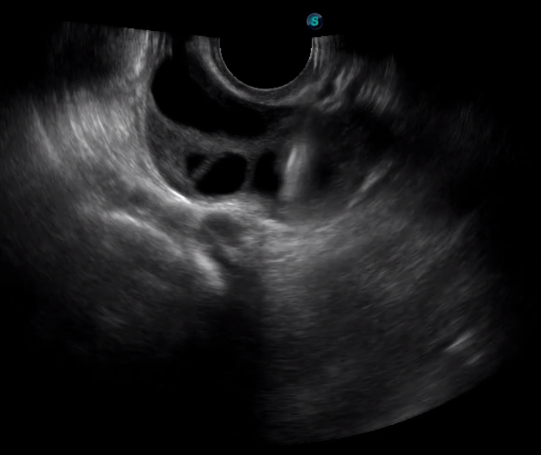

TEE(經(jīng)食道超聲心動(dòng)圖)將超聲探頭置入食道內(nèi),從心臟的后方向前近距離探查其結(jié)構(gòu) ,克服了經(jīng)胸超聲檢查的局限性,避免肺內(nèi)氣體、胸壁脂肪、胸廓畸形等因素影響,觀察角度更多,圖像更加清晰,測(cè)量數(shù)據(jù)更準(zhǔn)確。

經(jīng)食道超聲 大動(dòng)脈短軸